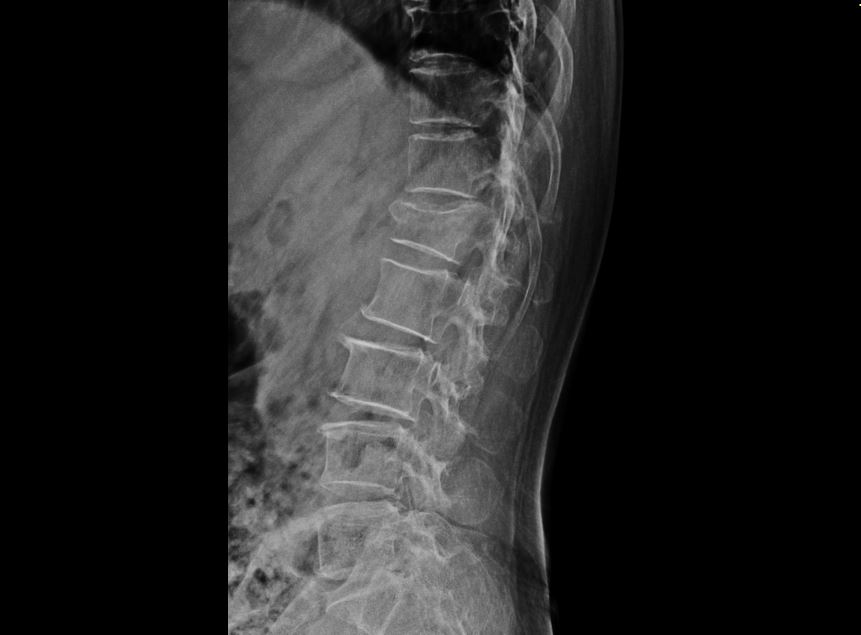

윤@@님은 눈길 미끄러짐으로 ** 요추 1번 골절 **진단을 받으셨습니다.

L1 부위의 골절 S32020

하지만 윤@@님은 골절의 정도가 심해 진단서에 쓰여있는 경피적 척추성형술골시멘트술을 받게 되셨는데요,